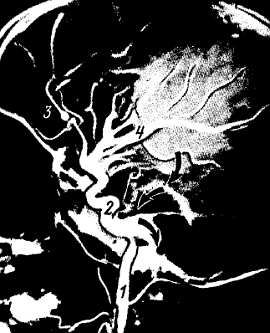

Селективная (избирательная) артериография артерий брюшной полости позволяет изучать чревный ствол, брыжеечные, почечные артерии и их ветви. При этом ясно заметно вхождение артерий в ворота органов, в частности селезенки, печени и почек (рис. 249).

Рис. 249. Артериография почки на живом человеке (по У. М. Ризаеву).

1 - почечная артерия: 2 - верхняя полярная артерия; 3 - срединная артерия; 4 - нижняя полярная артерия; 5 - междолевые артерии.

При рентгенографии артерий паренхиматозных органов видны не только экстраорганные сосуды, но и интраорганные.